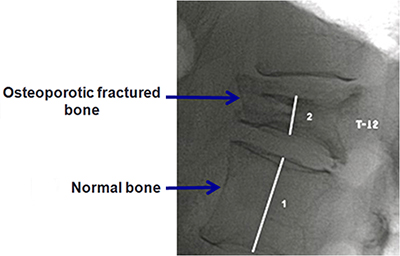

Osteoporosis of the spine

Osteoporosis means decrease in the bone density, this usually occurs in old age, when there is loss of calcium and essential elements from the bone leading to decrease in the bone density and thus they become weak.

Commonly it is also seen in women post menopause and in some who have undergone hysterectomy. Sometimes it can also occur in people who have medical conditions like Diabetes Mellitus, Thyroid disorders and other inflammatory conditions causing loss of bone calcium. Thus in these individuals it may occur at an early age also.

Weak bones mean they are most likely to get broken or fractured in simple falls or injuries, especially the vertebral column bones. These bones if fractured take a long time to heal as the bones are less dense and hence the materials required to rebuild the fractured bones are missing.